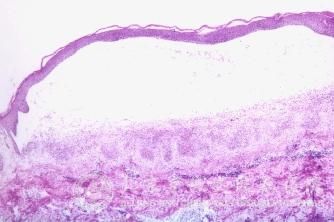

化妆品引起的皮炎的类型有什么?化妆品引起的皮炎是常见的一种皮肤病,化妆品引起的皮炎经常给人带来无尽的烦恼和痛苦,因此很多人会问这个化妆品引起的皮炎的问题。化妆品引起的皮炎给人们的生活工作带来了严重的影响,因此及时了解化妆品引起的皮炎的类型有什么,可以有助于我们及早的发现化妆品引起的皮炎,以及治疗化妆品引起的皮炎的皮肤症状。

多数患者在使用化妆品后数小时即发生过敏现象,这在医学上称立即型(或速发型)过敏反应;经过数天才发生过敏反应的则称为迟发型反应。